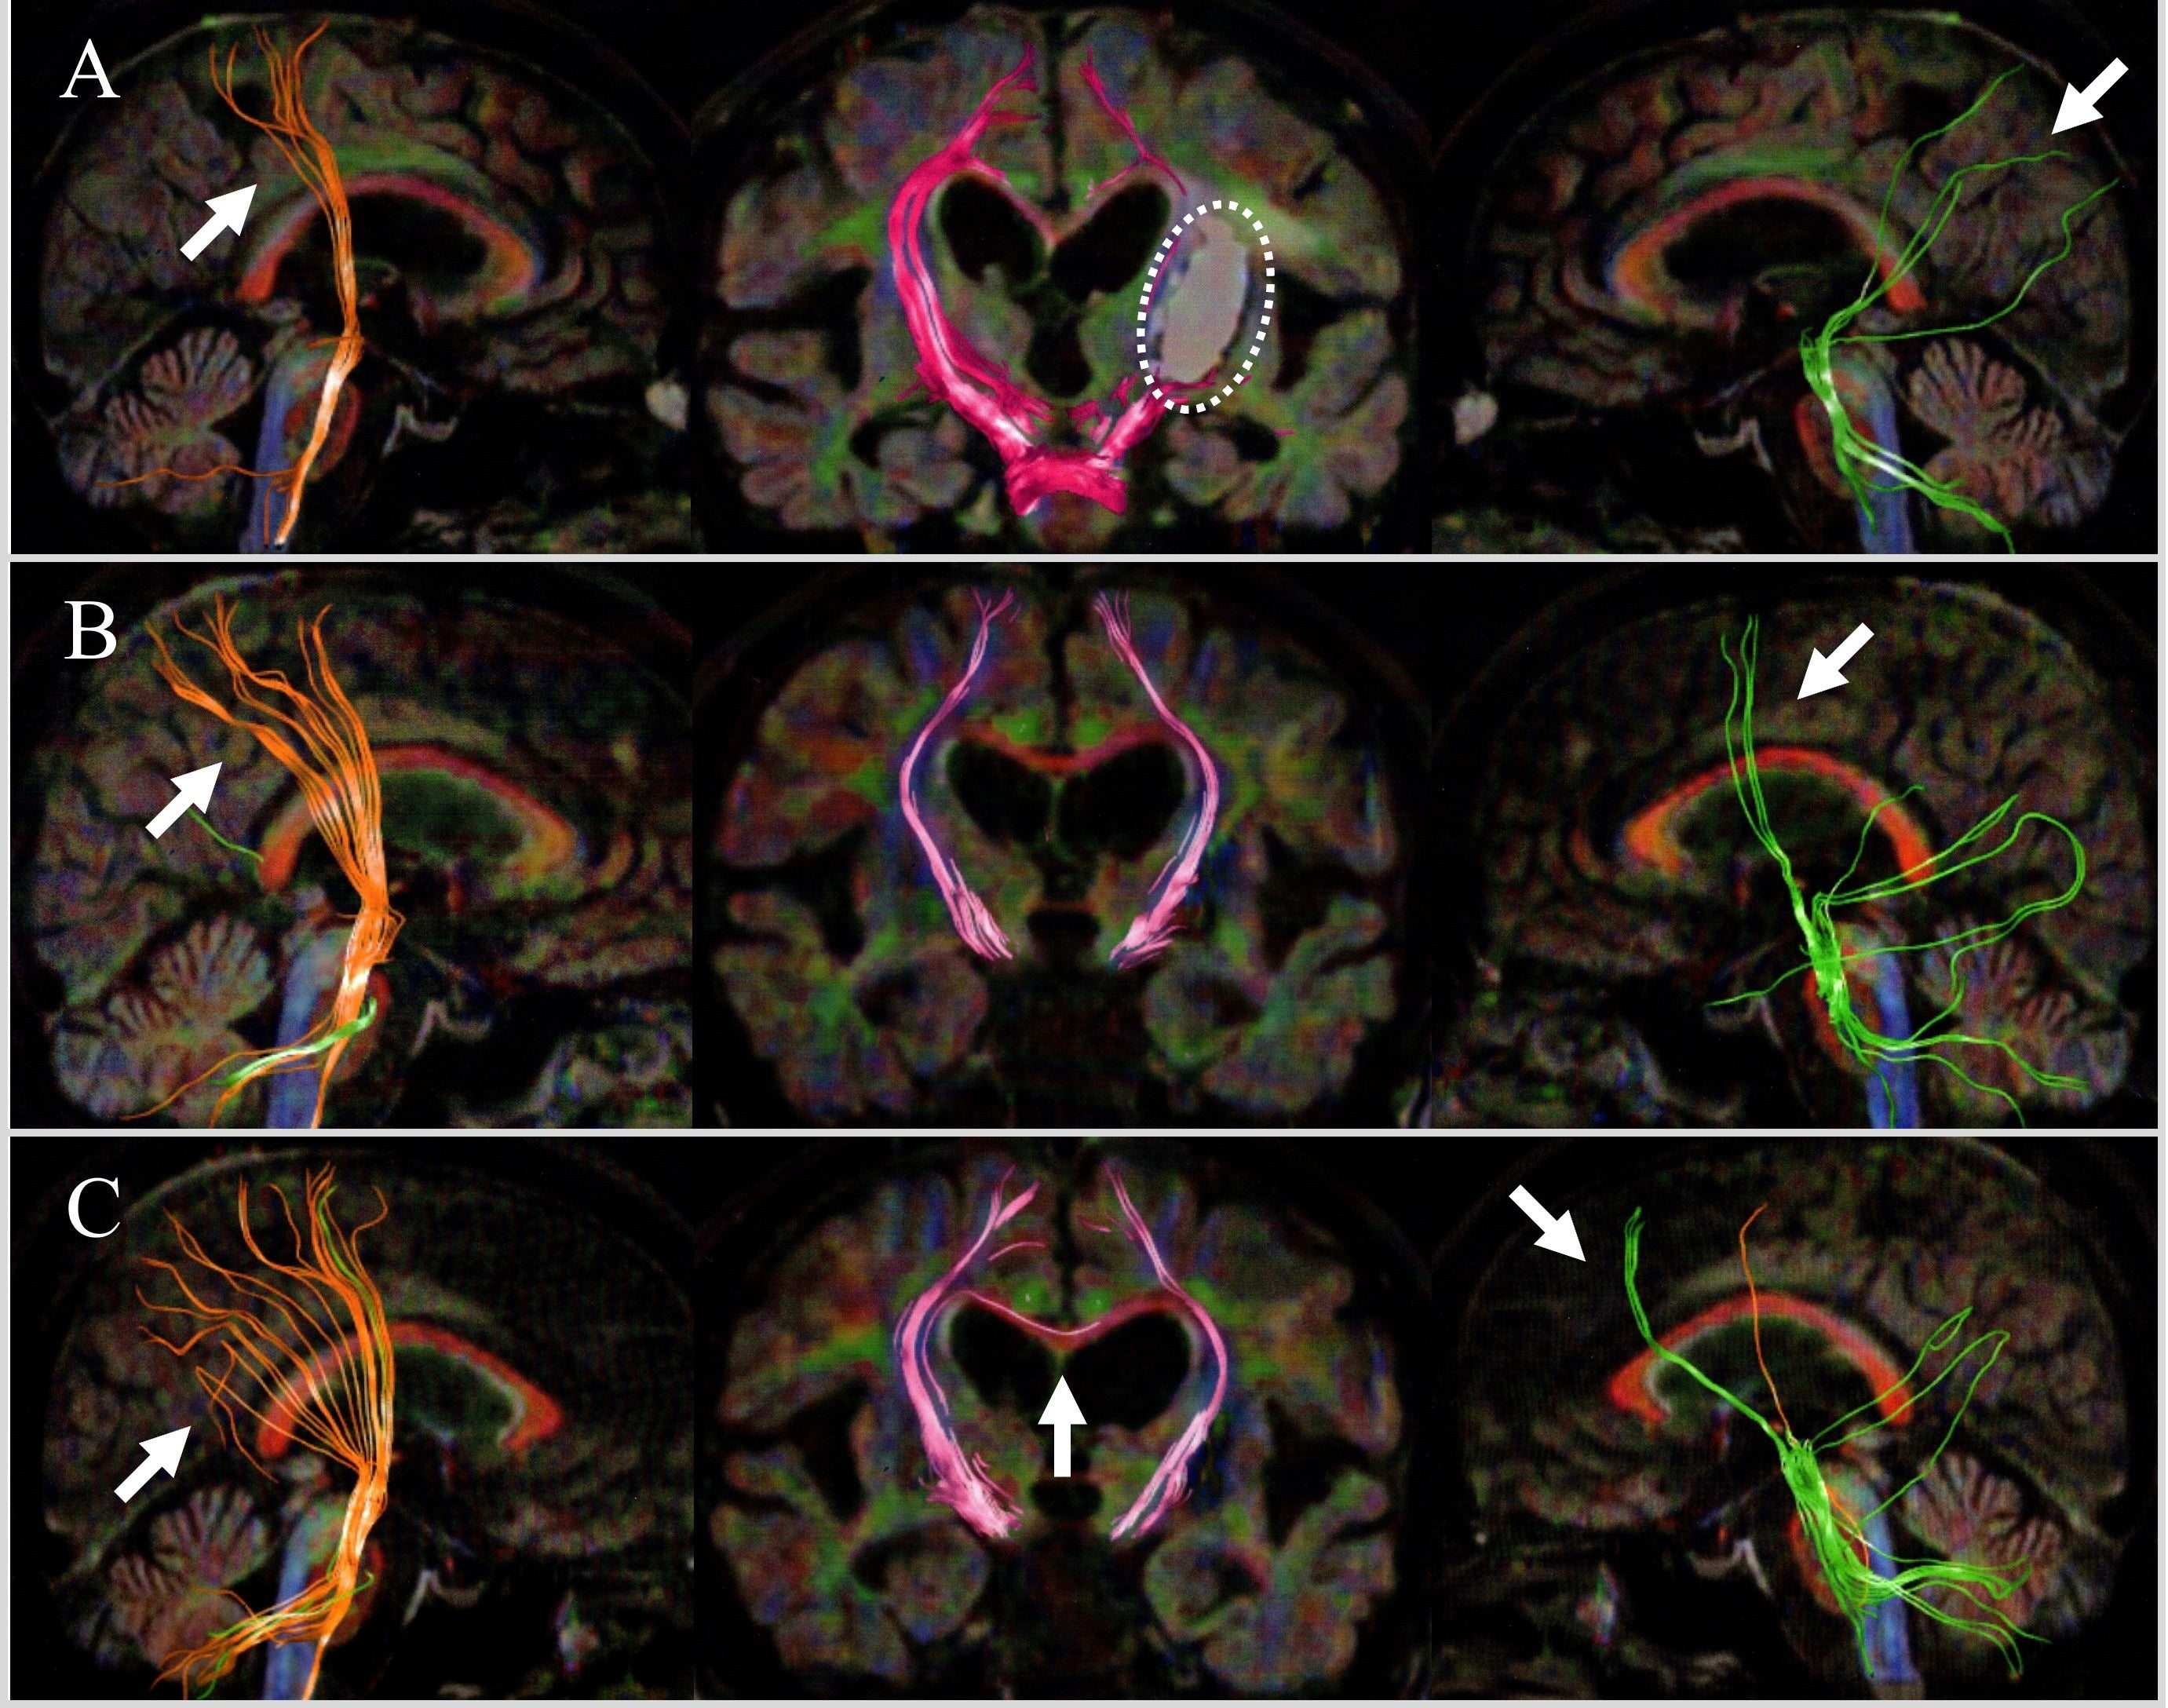

本論文では、mediVRが独自開発した「体性認知協調療法(SCCT)」と呼ばれるVRリハビリテーションにより、「回復の停滞期(プラトー)」にあるとされた脳卒中後片麻痺患者において、臨床的な運動機能の改善とともに脳内の運動神経回路が再構築される過程を、拡散テンソルトラクトグラフィー(Diffusion Tensor Tractography, DTT)画像を用いて可視化しました。

本症例報告における学術的意義は、維持期に近い段階(発症5ヶ月後)の被殻出血後片麻痺患者において、介入前後での拡散テンソルトラクトグラフィーの縦断的変化を詳細に捉えた点にあります。

皮質からの運動下降路のシフト:損傷側において、運動出力の源が頭頂葉後部から補足運動野、そして運動前野へと前方へシフトしていく過程を確認しました。

多面的な再構築:同時に、非損傷側の経路や小脳との結合の強化、脳梁線維の一過性の変動など、全脳にダイナミックな変化が生じ、臨床的な回復(Brunnstrom Stage IIからIIIへの改善)と関連して認められました。